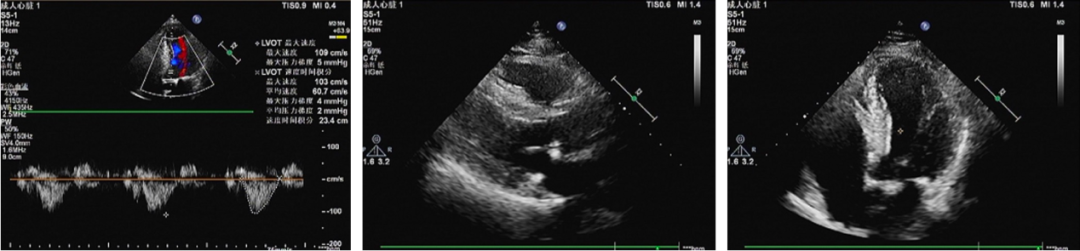

超声检查

心脏彩超:1、主动脉瓣置换后生物瓣重度狭窄合并重度关闭不全;主动脉瓣瓣口流速Vmax 4.24m/s,峰值跨瓣压差72mmHg,平均跨瓣压差36mmHg,瓣环内径20.9mm,升主34.2mm。2、左房增大;3、升主动脉增宽;4、室间隔增厚;5、二尖瓣、三尖瓣及肺动脉瓣返流(轻度);6、左室舒张顺应性减退。

术后评估

主动脉瓣术后平均压差7mmHg,无瓣周漏。